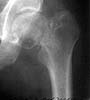

A miner 38 y.o. referred to us with 5 months old femoral neck lesion - after direct impact by a heavy construction he probably had non-displaced neck fracture. 3 months of spica cast, then non-weight-bearing. AP view and CT scan attached. Looks like AVN is present. ROM is painless and full, loading is also painless.